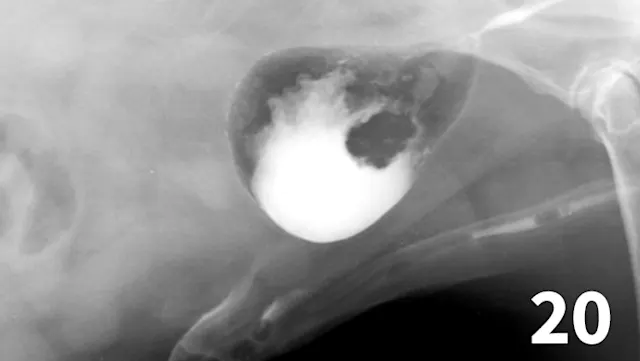

Double-contrast cystography can be an excellent tool to evaluate bladder wall thickness and any irregularities of the bladder mucosal surface and to rule out the presence of radiolucent cystouroliths (Figure 20). Although double-contrast cystography is more invasive because of the need for urethral catheterization, artifactual bladder wall thickening is usually not an issue because the degree of bladder distention can be controlled.